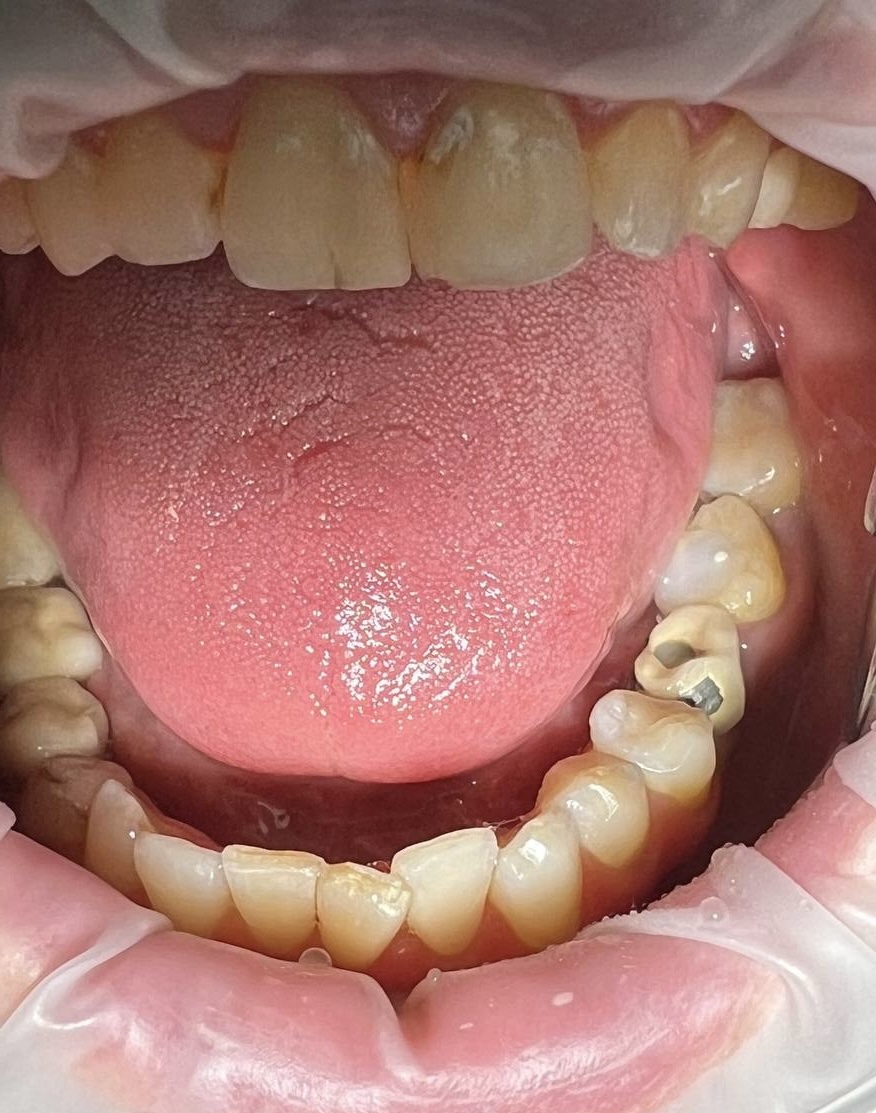

Замена старой металлокерамической коронки на циркониевую коронку на импланте в области 3.6. Протезирование зуба 3.7 циркониевой коронкой

В течение недели изготовлены и установлены циркониевые коронки на имплант 3.6 и зуб 3.7.